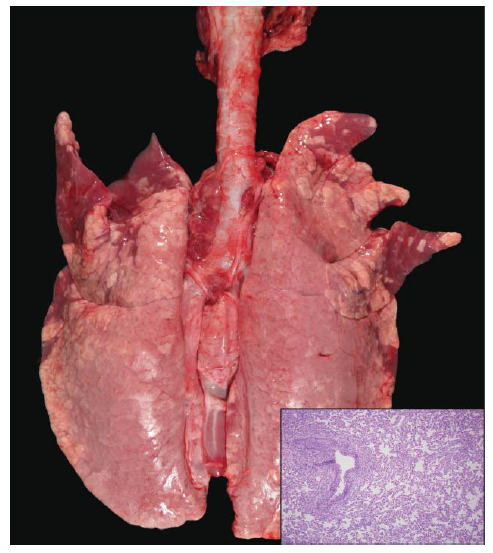

Meskipun beberapa lesi dapat terlihat dalam waktu 48 jam setelah PI, lesi makros belum berkembang secara penuh dan hanya dapat mewakili setengah dari lesi mikroskopis yang telah terjadi [13]. 5 hari setelah PI, pola lobular multifokal sampai lesi yang menyatu lebih konsisten dalam merefleksikan lesi mikroskopis. Sebagai contoh, keberadaan lobular ateletaksis terlihat secara makros sebagai wilayah poligonal konkaf, berwarna merah tua yang keras dan tebal ketika diraba (Gambar 16.3). Lobular dan lobar ateletaksis juga terlihat pada infeksi M. Hyopneumoniae, dan secara makroskopis bisa saja tidak dapat dibedakan dengan infeksi virus AI. Area poligonal yang terlihat membesar, berwarna merah tua sampai ungu yang sering dideskripsikan sebagai teraba seperti “hepar” atau memiliki tampilan seperti “daging” (meaty) merefleksikan konsolidasi alveolar (celah alveolar yang dipenuhi debris selular, sel radang, dan cairan edema). Lesi makroskopis ini lebih merupakan karakteristik infeksi bakteri aerosol dalam paru-paru dan dalam kasus infeksi AI sering dihubungkan dengan PRDC atau infeksi sekunder bakteri.

Gambar 16.3 Lesi makroskopis dalam paru-paru pada babi berumur 4 minggu yang secara eksperimental diinokulasi dengan virus H1N1 A/swine/illinois/02450/2008 5 hari setelah PI. Lesi lobular yang saling menyatu berwarna merah tua terletak di bagian cranioventral paru-paru, dan lesi mikroskopis (dalam insert) menunjukkan ateletaksis. Sumber: Susan Detmer.